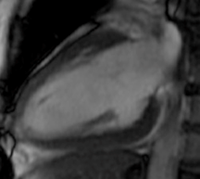

心臓MRI

MRI(磁気共鳴画像診断法:Magnetic Resonance Imaging)は、強力な磁石と電磁波を用いて、身体各所の断層像を観察できる検査です。

心筋の壁運動の評価や心筋の繊維化(ダメージを受けた部位)の評価を行います。